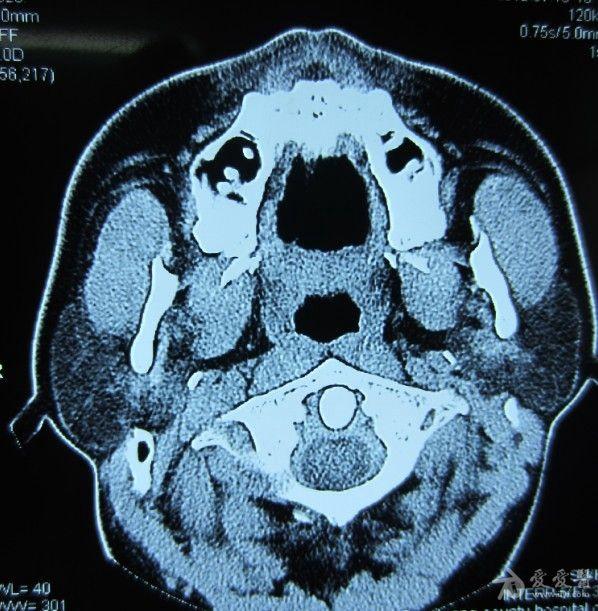

诊断:tornwaldts囊肿(鼻咽潴留囊肿)

2.mri ct鉴别咽囊囊肿,腺样体肥大,鼻咽部肿瘤困难时可行mri扫描.1.

图2 咽囊囊肿a.mri横断面t1wi示鼻咽后壁正中类圆形突起呈低信号;b.